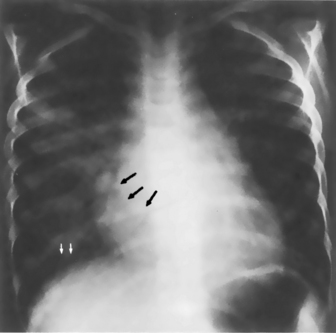

image image

Fig. 10-5 Pleural effusion. These films were obtained when this 3-year-old child developed tachypnea and increased respiratory effort several days after repair of a double-outlet right ventricle. The nurse noted a significant decrease in breath sounds over the right lung fields, particularly the right middle and lower lobes. The right lung fields were dull to percussion. The radiograph was ordered to differentiate between atelectasis and pleural effusion. A, The upright anteroposterior film. Despite an apparently good inspiratory film, the right lung field is smaller than the left. This finding could indicate elevation of the diaphragm as a result of atelectasis. It also could represent free pleural fluid accumulation along the diaphragm. The hilar pulmonary vascular markings are somewhat hazy; this is consistent with either atelectasis or compression of the right lung by subpulmonic fluid. The right costophrenic angle is blunted, so the diagnosis of pleural effusion was favored and a decubitus film was ordered to confirm the diagnosis. B, The decubitus film. The film was taken with the child lying on his right side so that the free right pleural fluid accumulated along that side. The fluid level is easily discerned (arrows).

(Courtesy Andrew K. Poznanski, Children’s Memorial Hospital, Chicago, IL.)